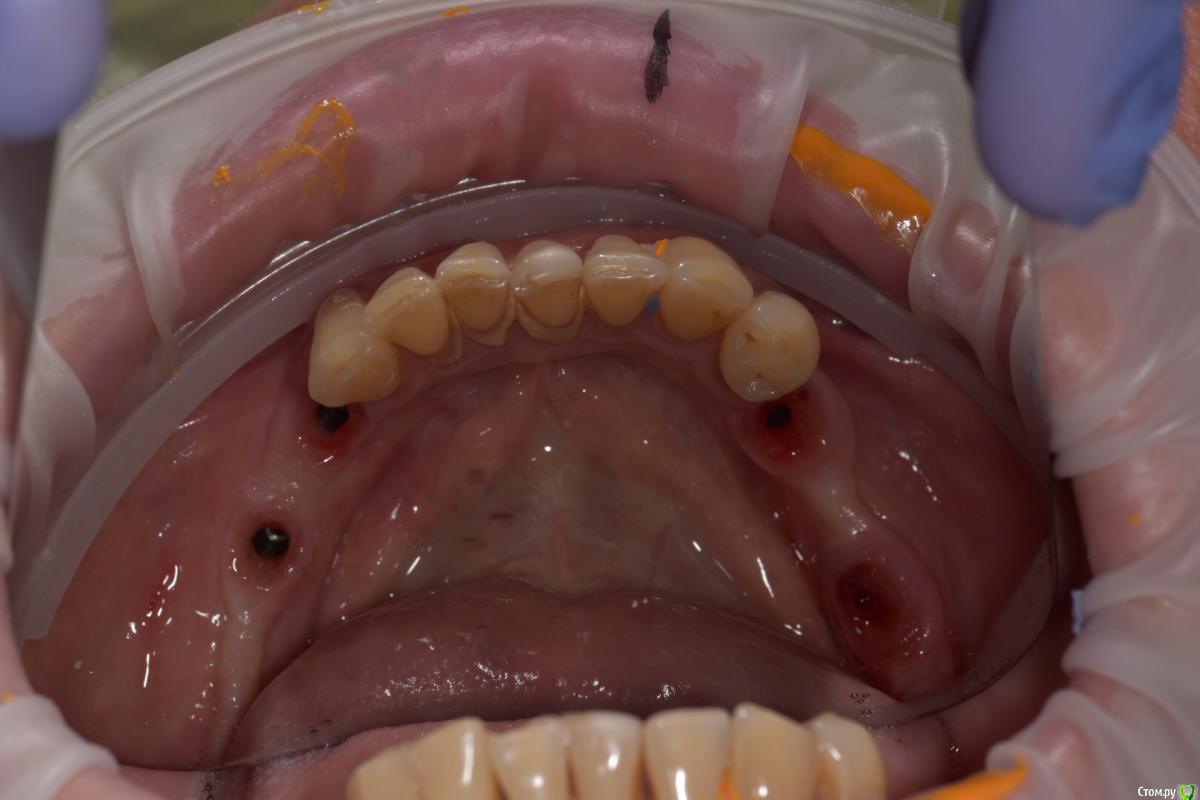

Santi Опубликовано 18 сентября, 2018 Поделиться Опубликовано 18 сентября, 2018 Имеем Концевые деффекты н/ч. Справа по плану НКР+импланты в позициях 4-6, слева импланты+ десна Итог сразу после Через 5-6 месяцев имеем такую картину Сразу после мягкотканной пластики И через пару месяцев Заранее пардоньте за качество фото и отсутствие картины ДО Ваше мнение коллеги ? 3 Ссылка на комментарий

Santi Опубликовано 19 сентября, 2018 Автор Поделиться Опубликовано 19 сентября, 2018 Этапов аугументации к сожалению нету. То , что выложил + этап раскрытия Ссылка на комментарий